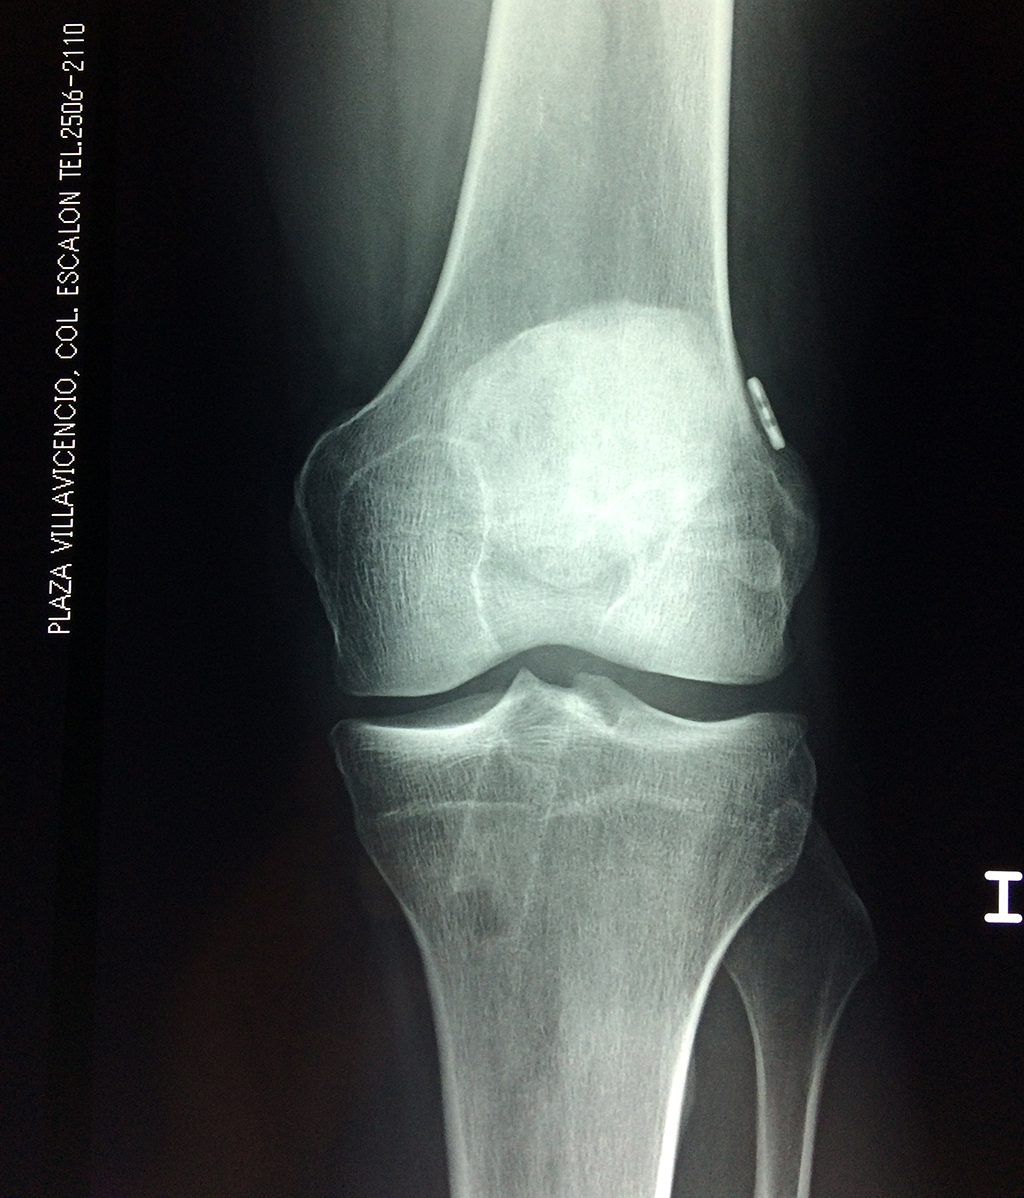

Fémur - Rodilla

La artroscopia de rodilla es un cirugía en el cual la estructura interna de la articulación es examinada ya sea para realizar un diagnostico o para realizar un tratamiento, este procedimiento se realiza utilizando un instrumento parecido a un pequeño tubo llamado artroscopio.